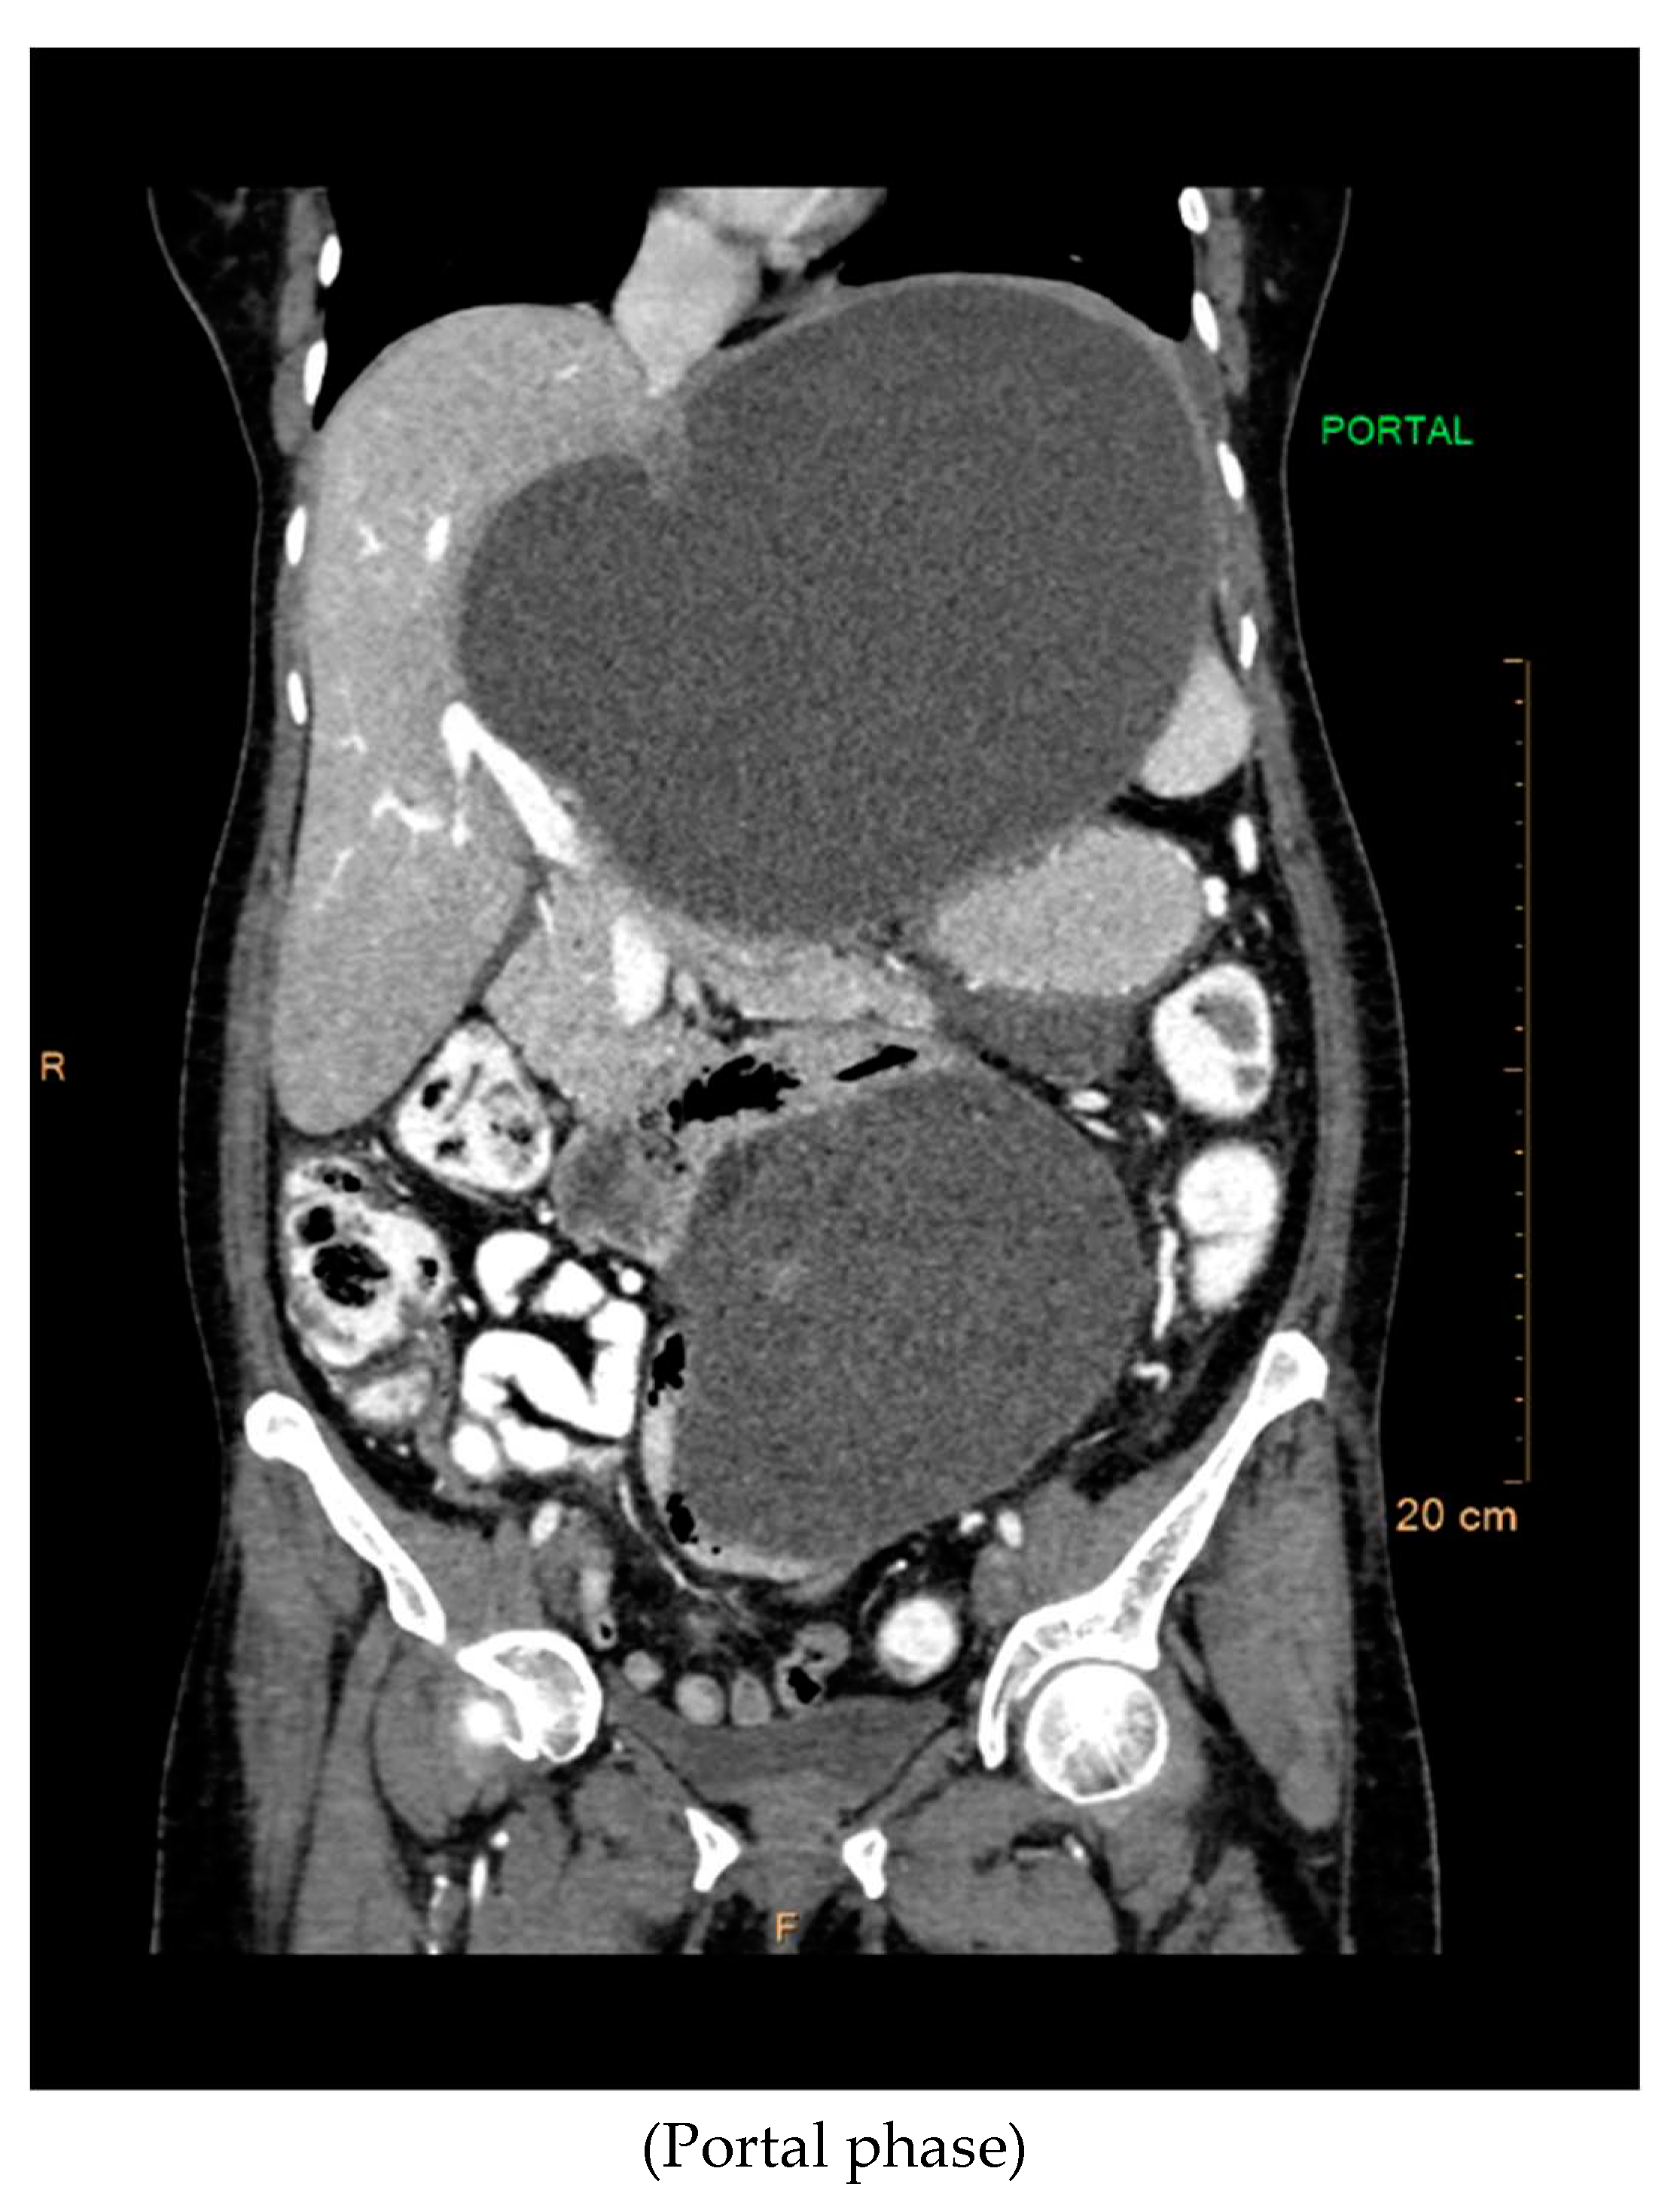

CT Contrast Abdomen Findings

The contrast-enhanced computed tomography (CT) findings reveal a series of notable features within the abdominal region. Multiple well-defined peripherally enhancing cystic lesions, each exhibiting internal septations, are observed in distinct locations, including the epigastric, gastrohepatic, left lumbar, and greater omentum regions along the greater curvature of the stomach. These cystic formations present as significant entities in the imaging, demonstrating a complex architecture.

Preprints 94567 g003

A large, well-defined peripherally enhancing cystic lesion with several internal enhancing septations is identified in the epigastric and gastrohepatic region. There is a possibility that this lesion originates from the left lobe of the liver. Notably, the superior extension of this lesion reaches up to the left hypochondriac and subdiaphragmatic regions. Laterally, it extends towards the left lateral abdominal wall, exerting pressure and indentation on the right lobe of the liver.

Inferiorly, the large cystic lesion exerts compression on the body of the stomach, causing displacement. Posteriorly, the lesion notably compresses the body of the pancreas. Further examination reveals compression on the common hepatic artery, portal vein, and splenic vein at the splenoportal junction, although these vessels remain patent. Anteriorly, the lesion extends up to the anterior abdominal wall, showcasing its expansive nature.

The posterior and left lateral aspects of the lesion result in the displacement and compression of the mid and upper pole of the spleen. Additionally, collateral vessels are observed in the perisplenic and left hypochondriac regions, indicating the potential impact of this cystic lesion on vascular dynamics. The comprehensive CT contrast findings provide valuable insights into the intricate anatomical alterations and potential clinical implications associated with these cystic lesions within the abdominal cavity.